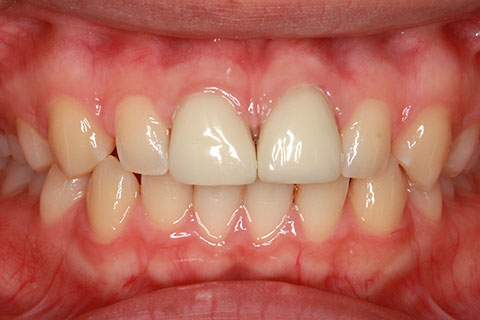

• オールセラミックの症例1

治療前

治療後

上顎前歯のデコボコと色調を改善。

年齢・性別

40歳女性

治療期間

1ヶ月

抜歯

なし

治療費

35.2万円

備考

前歯4本の変色歯及び歯列不正によるセラミック治療

治療内容

歯質を削除し、セラミック冠をセメント合着

施術の副作用(リスク)

知覚過敏、歯髄炎、荷重負担